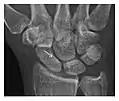

High-energy trauma fractures

Occult osseous injuries may result from a direct blow to the bone by compressive forces of adjacent bones against one another or by traction forces during an avulsion injury. Lesions in the tibial plateau, hip, ankle, and wrist are often missed. In a tibial plateau fracture, any disruption of the posterior and anterior cortical rims of the plateau should be sought. Impaction of subchondral bone will appear as an increased sclerosis of the subchondral bone (Figure 1). In the hip, posterior acetabular fractures also present subtle radiographic findings. The acetabular lines should then be carefully examined keeping in mind that the posterior rim, which is harder to see on X-rays, is more frequently fractured than the anterior rim (Figure 2). In the wrist, detection of carpal bone fractures is often challenging, with up to 18% of scaphoid fractures radiographically occult. Carpal fractures, especially the scaphoid, are associated with the risk of avascular necrosis. In apparently normal wrist radiographs from symptomatic patients, if there is history of a fall on an outstretched hand with pain in the anatomic snuffbox, suggesting scaphoid injury, the initial examination with posteroanterior, lateral, and pronation oblique views must be complemented by other specific views such as supination oblique and the "scaphoid" view A careful examination of cortices for evidence of discontinuity or offset and cancellous bone for lucency is necessary (Figure 3).[1]

Triquetral fracture usually occurs on the dorsal aspect by impingement from the ulnar styloid or avulsion of strong ligamentous attachment. The dorsal avulsion fracture or "chip fracture" appears as a small bony fragment on the dorsal aspect of the triquetrum and is best detected on the lateral view(Figure 4). When radiography is negative in patients with high suspicion of a fracture, both MRI and MDCT will be of value. However, it has been shown that MRI is superior for detecting trabecular fractures in carpal bones.

a

b

Figure 4: Dorsal triquetral fracture of the left wrist in a 30-year-old man after a trauma. (a) Anteroposterior radiograph shows a normal appearance. (b) Lateral radiograph of the same wrist demonstrates a chip fracture off the dorsal aspect of the triquetrum (arrow).[1]